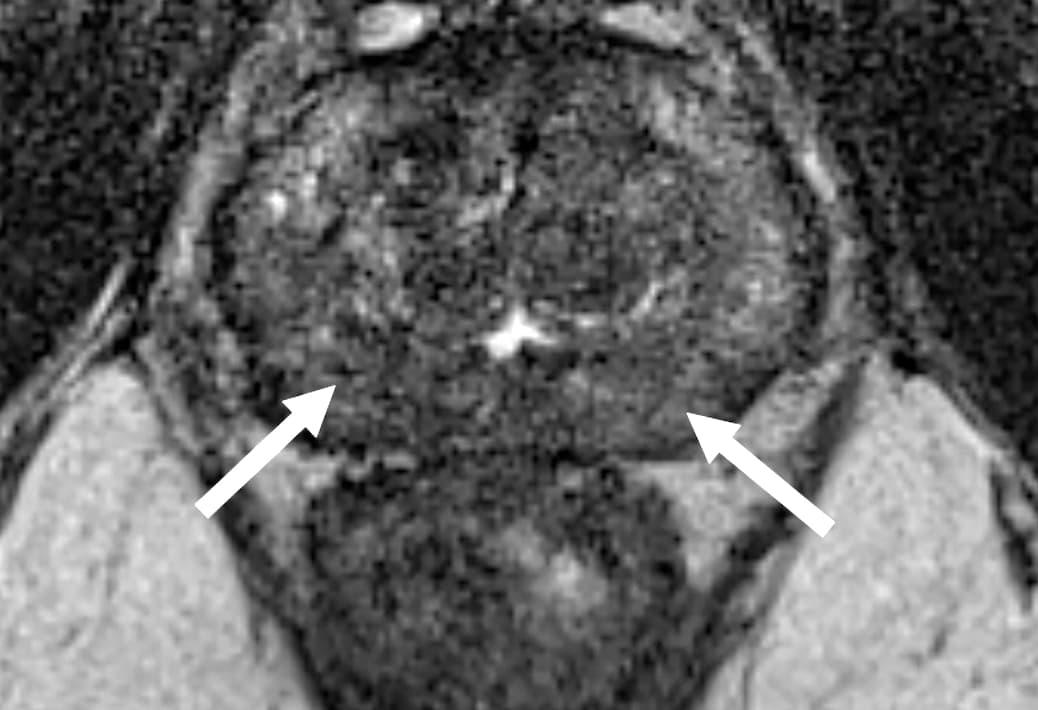

Le Liver Imaging Reporting and Data System (LI-RADS), qui est destiné à classer les lésions à type de carcinome hépatocellulaire (CHC) chez les patients à haut risque atteints de cirrhose ou d'infection chronique par le virus de l'hépatite B est divisé en sept catégories principales en fonction de leur probabilité d'être un CHC (LR-1 à LR-5), une lésion maligne non spécifique au CHC (LR-M) ou une tumeur veineuse (LR-TIV).

La résection chirurgicale et l'ablation locale sont les options de traitement pour les patients atteints d'un CHC unique et d'une fonction hépatique préservée, malgré un risque de récidive élevé, selon des taux allant jusqu'à 70 % des patients dans les 5 ans. Les caractéristiques et les catégories LI-RADS chez les patients atteints d'un carcinome primitif du foie, y compris le CHC et d'autres tumeurs malignes primaires non CHC sont désormais bien référencées.

Une survie sans maladie (DFS) et une survie globale (SG) semblent notamment plus courtes chez les patients avec des lésions classées comme LR-M que chez les patients avec des lésions classées comme LR-3, LR-4 ou LR-5 après une résection chirurgicale. Cependant, les caractéristiques histopathologiques de la tumeur telles que la taille, le grade, l'invasion macro-vasculaire et microvasculaire, les nodules satellites et la capsule tumorale sont également connues pour être associées à un risque accru de récidive chez les patients atteints de CHC réséqué.